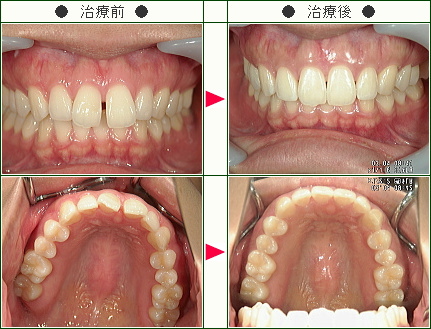

☆前歯のすきっ歯矯正症例[ちか様 25歳 女性]